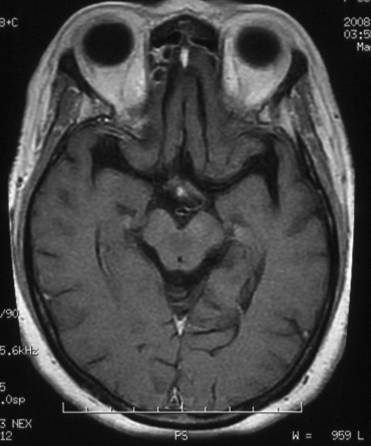

天幕脑膜瘤:

治疗前

治疗后